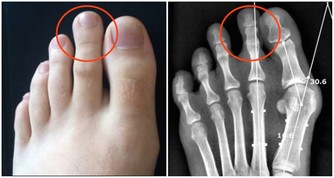

腳上出現這物,竟是心臟病信號。腳部出現青筋腳面部位本來是平坦無皺紋的,如果表面出錢青筋凸起,說明腳部的血液循環開始出現受阻現象。

雖然身體暫時感覺不到其他的不適癥狀,但是我們千萬不可以忽視這一癥狀。

往往大病之前總是潛伏著一些小毛病。